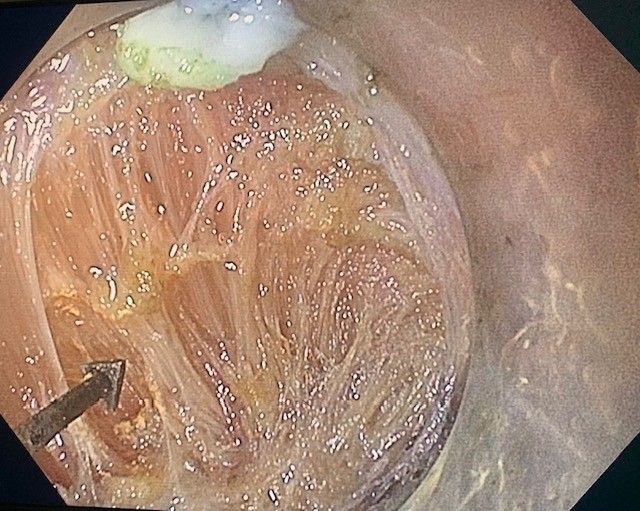

Given the significant time elapsed since her previous evaluation, our team deemed an updated EGD appropriate. On initial introduction of EGD into the inlet, a moderate-sized, Zenker diverticulum was noted (Figure 1). The rest of the esophagus and GE junction were grossly normal. After the diagnosis of Zenker diverticulum, we discussed various options with the patient, and the shared decision was made to proceed with Zenker peroral endoscopic myotomy (Z-POEM) for the definitive treatment of her dysphagia.

Figure 1: Pre-procedure esophagogastroduodenoscopy showing a Zenker diverticulum without luminal contents.

Figure 1